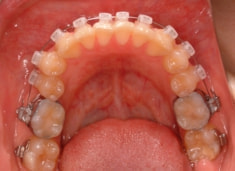

治療法:表の矯正(T21ブラケット)

治療開始時